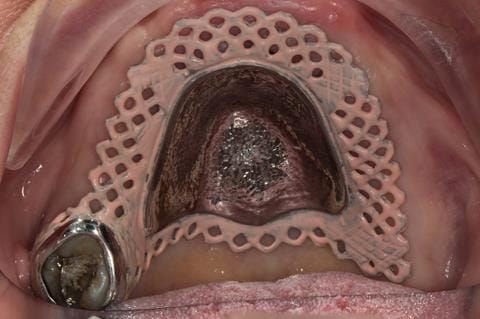

- Poorly fitting cobalt chromium based maxillary partial denture, which has been added to. This exhibited poor retention, stability and tissue fit (support). Unable to wear a new acrylic based denture.

- Cobalt chromium reinforced gasket denture - using a Molloplast B "O" ring to retain and stabilise the denture. This was my professional preference as this was the least invasive and simplest solution to this dental problem. Should the UR7 require removal in the future - an artificial tooth could be added - resulting in a complete denture. The patient would have adapted to the denture fully by this stage and have good neuromuscular control of the prosthesis.

Following consultation and second discussion appointment the patient chose to have option 2 namely, a window denture - maxillary cobalt chromium based partial denture. The clinical situation and treatment process is shown in detail below with photographs. The patient was successfully rehabilitated with this and her quality of life considerably improved. The clinical work was provided by Finlay and the technical work by Rowan.